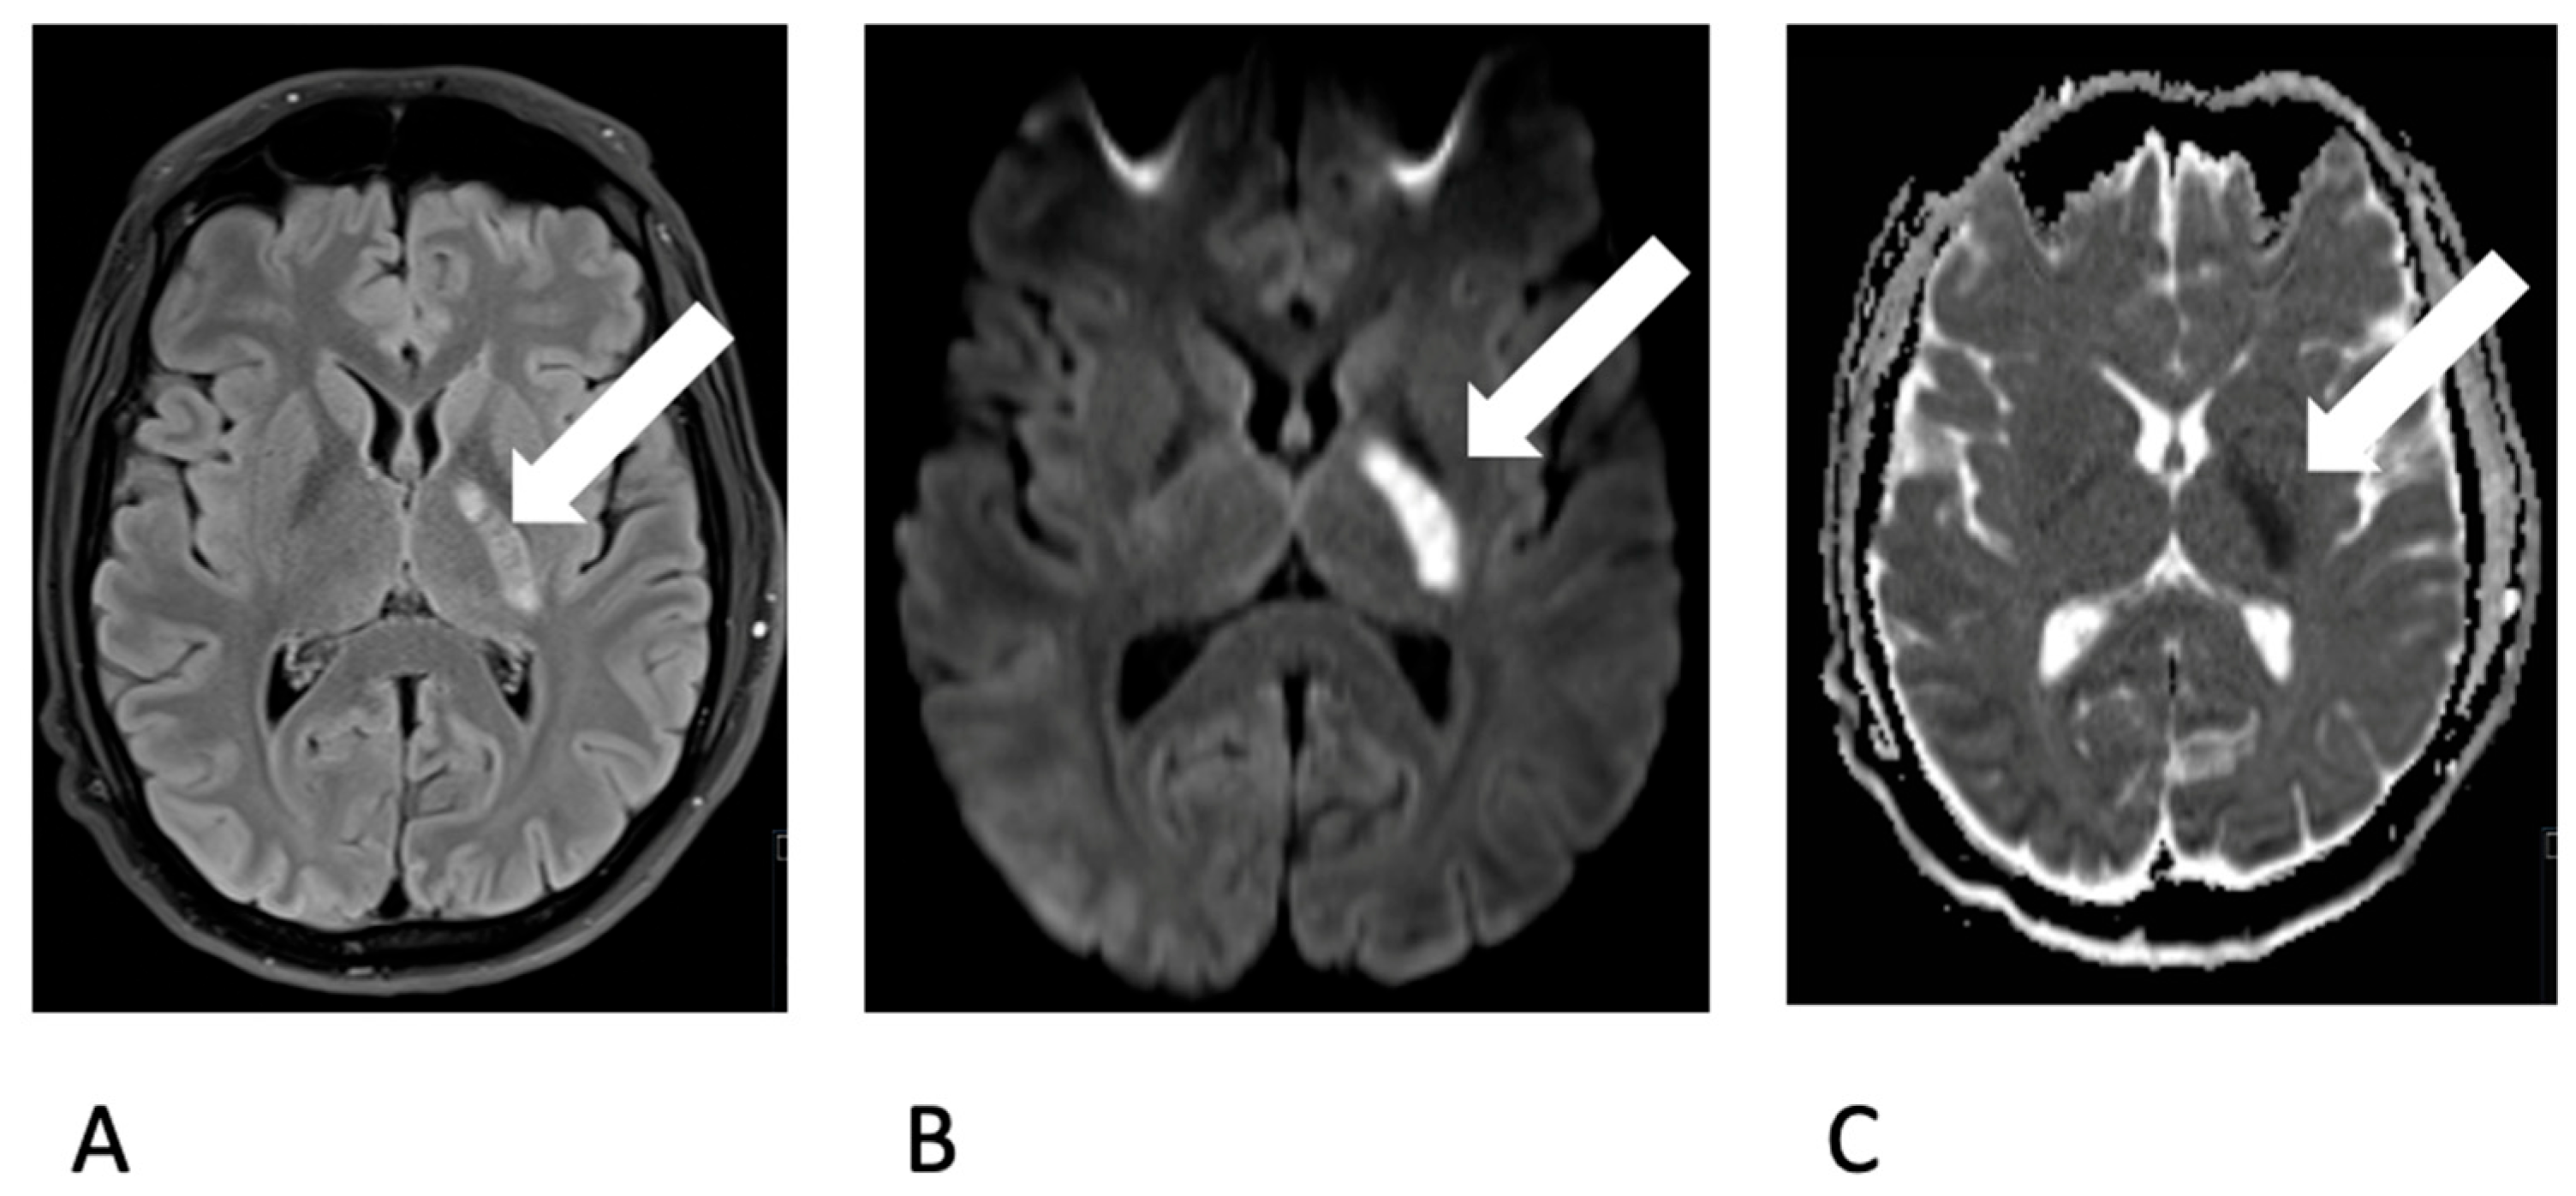

The previously healthy young man, without any cardiovascular risk factors, had undergone wisdom tooth extraction one week prior. Following the procedure, he developed symptoms such as fever and a general sense of illness. A cranial CT scan was conducted, indicating a demarcated infarct in the posterior crus of the left internal capsule, characterized by hypodensity. A lumbar puncture revealed the presence of lymphomonocytic cells (approximately 800 cells) and elevated lactate levels, consistent with a diagnosis of bacterial meningitis accompanied by vasculitis. Triple therapy with ceftriaxone, ampicillin, and aciclovir was initiated. An MRI scan confirmed CT findings (Figure 1).

Figure 1.

Depiction of an ischemic lesion (white arrow) in the posterior limb of the left internal capsule (A. choroidal artery territory) on MRI. Demarcation on T2 FLAIR-w image (A) and Diffusion restriction on b1000 image (B) and ADC map (C).